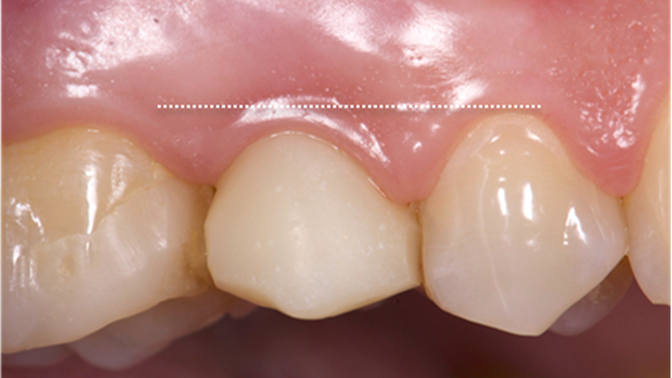

Clinical case: Extraction, immediate implant placement, & provisionalization

- Courtesy of Dr. Iulian Filipov, Romania -

Keywords

AnyRidge, R2GATE, guided surgery, immediate placement, immediate provisionalization, initial stability, Dr. Iulian Filipov, #25, maxillary posterior, immediate loading, Mega ISQ